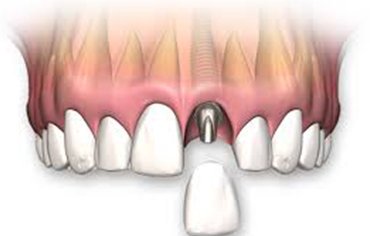

DENTAL IMPLANT is an artificial root placed into the jaw to hold a MISSING TOOTH.

After clinical examination and radiographic assessment[ CBCT, OPG], a small opening is made in the gums to expose the bone. Surgical guides are prepared and implant made up of TITANIUM is placed. Once the IMPLANT is placed, bone is deposited and the implant unites with the bone. After placing the implant perfectly, ABUTMENT is placed . Abutment is a post that connects implant to the prostetic tooth. After 2-3 weeks artificial tooth is placed.